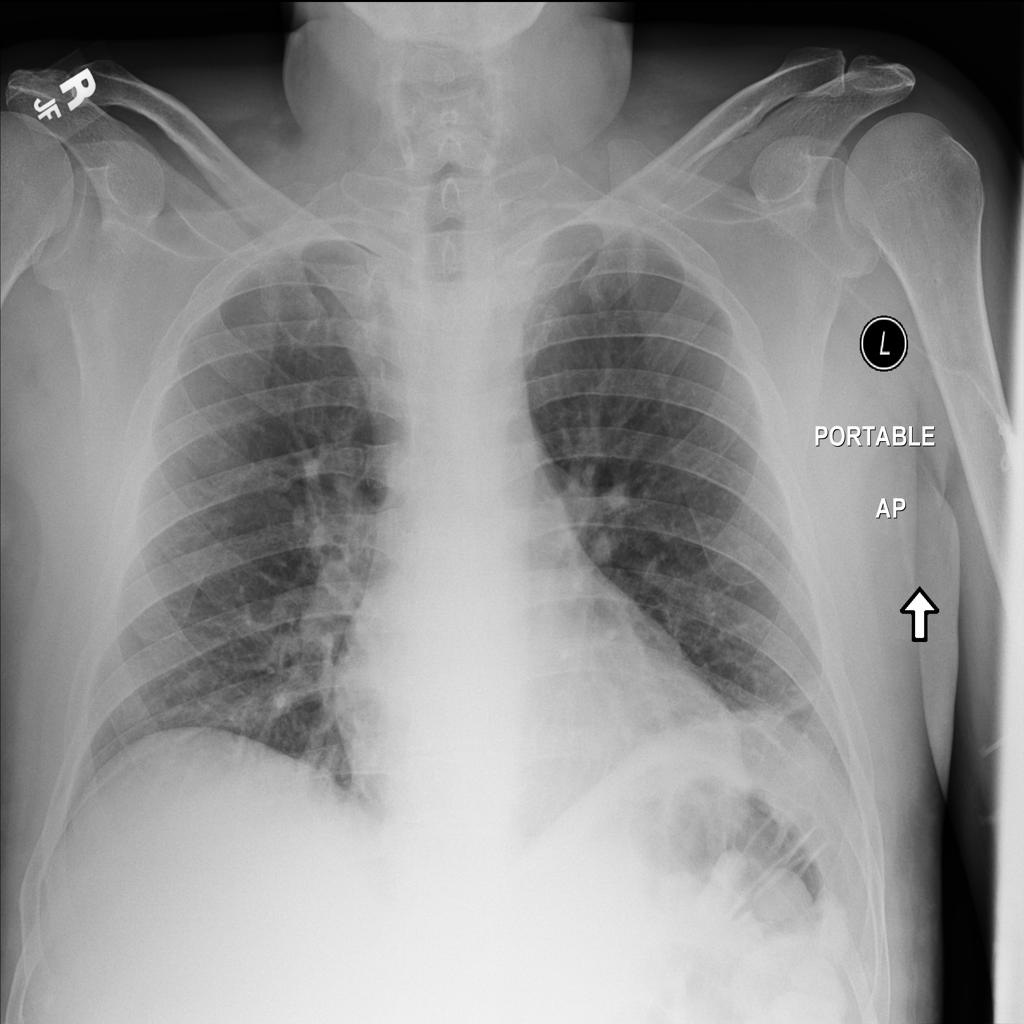

PAT-5446 · IMG-001Atelectasis

PAT-5446 · IMG-001

AP